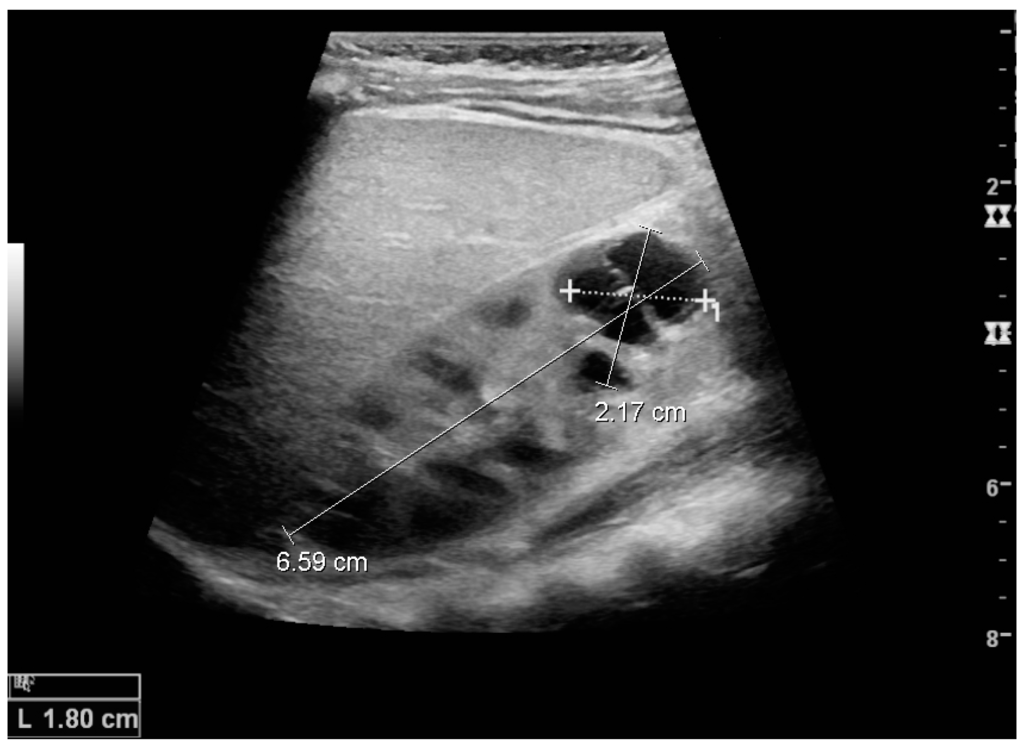

Complex cysts can have membranes dividing the fluid-filled center with internal echoes, calcifications or irregular thickened walls. The complex cyst can be further evaluated with Doppler US, and for Bosniak classification and follow-up of complex cysts, either contrast-enhanced ultrasound (CEUS) or contrast-enhanced computed tomography (CT) are used (Figure 6) [14,15]. The Bosniak classification is divided into four groups going from I, corresponding to a simple cyst, to IV, corresponding to a cyst with solid parts and an 85%–100% risk of malignancy [13,16].

Figure 6. Complex cyst with thickened walls and membranes in the lower pole of an adult kidney. Measurements of kidney length and the complex cyst on the US image are illustrated by ‘+’ and dashed lines.